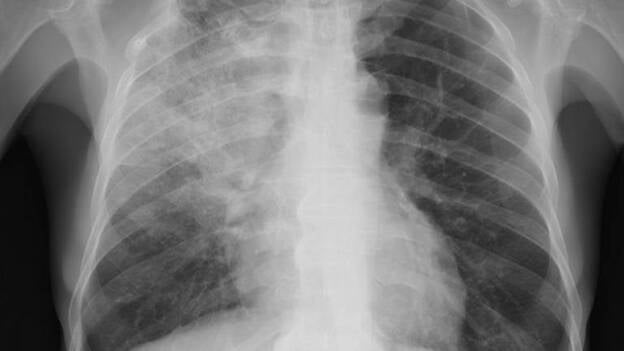

18 jul 2016 11:39 José Antonio Caminero: "Falta un plan que controle al paciente con tuberculosis" Odra Rodríguez Santana

30 jun 2016 15:44 Un estudio alerta de que muchos adultos en España continúan desarrollando neumonía adquirida en la comunidad Europa Press